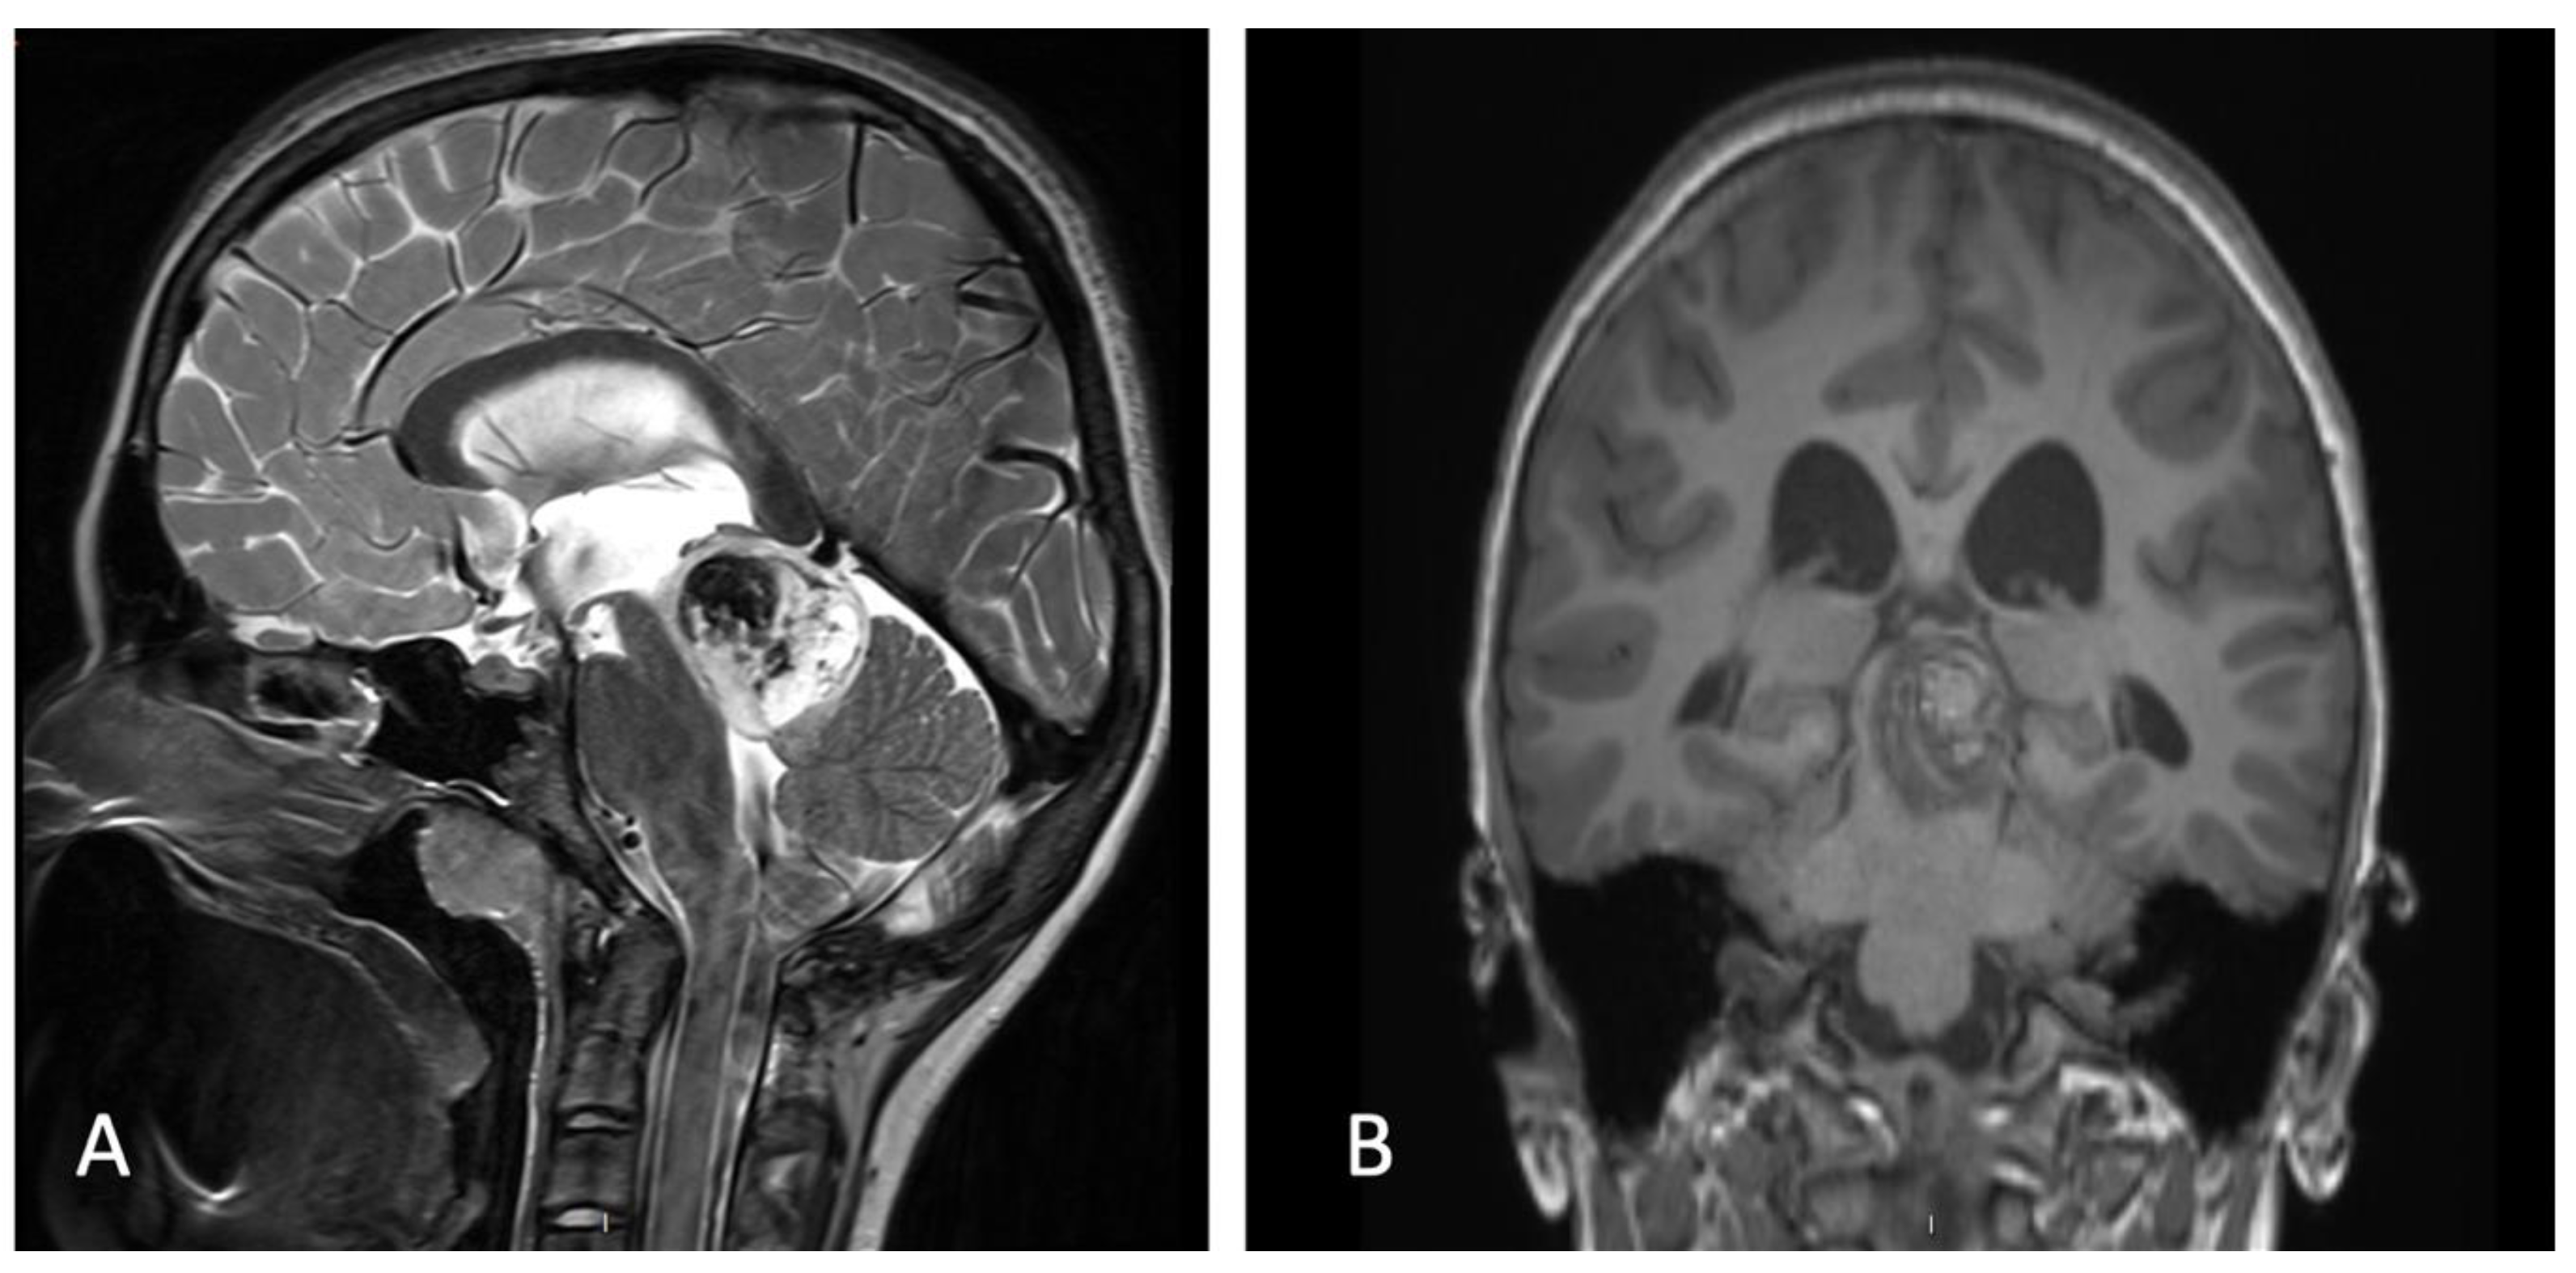

2. Case Presentation